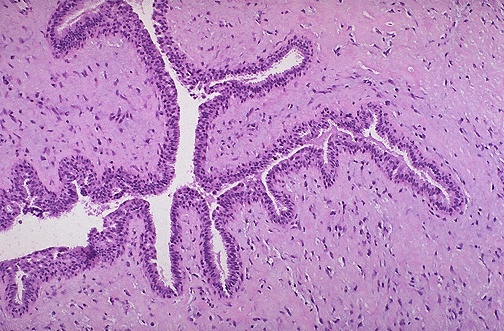

A phyllodes tumor of the breast is shown here. They arise from interlobular stroma, but unlike fibroadenomas are not common and are much larger. They are low-grade neoplasms that rarely metastasize. They are more cellular than fibroadenomas. Projections of stroma into the ducts create the leaf-like pattern for which these tumors are named (from the Greek word phyllodes meaning leaf-like). |